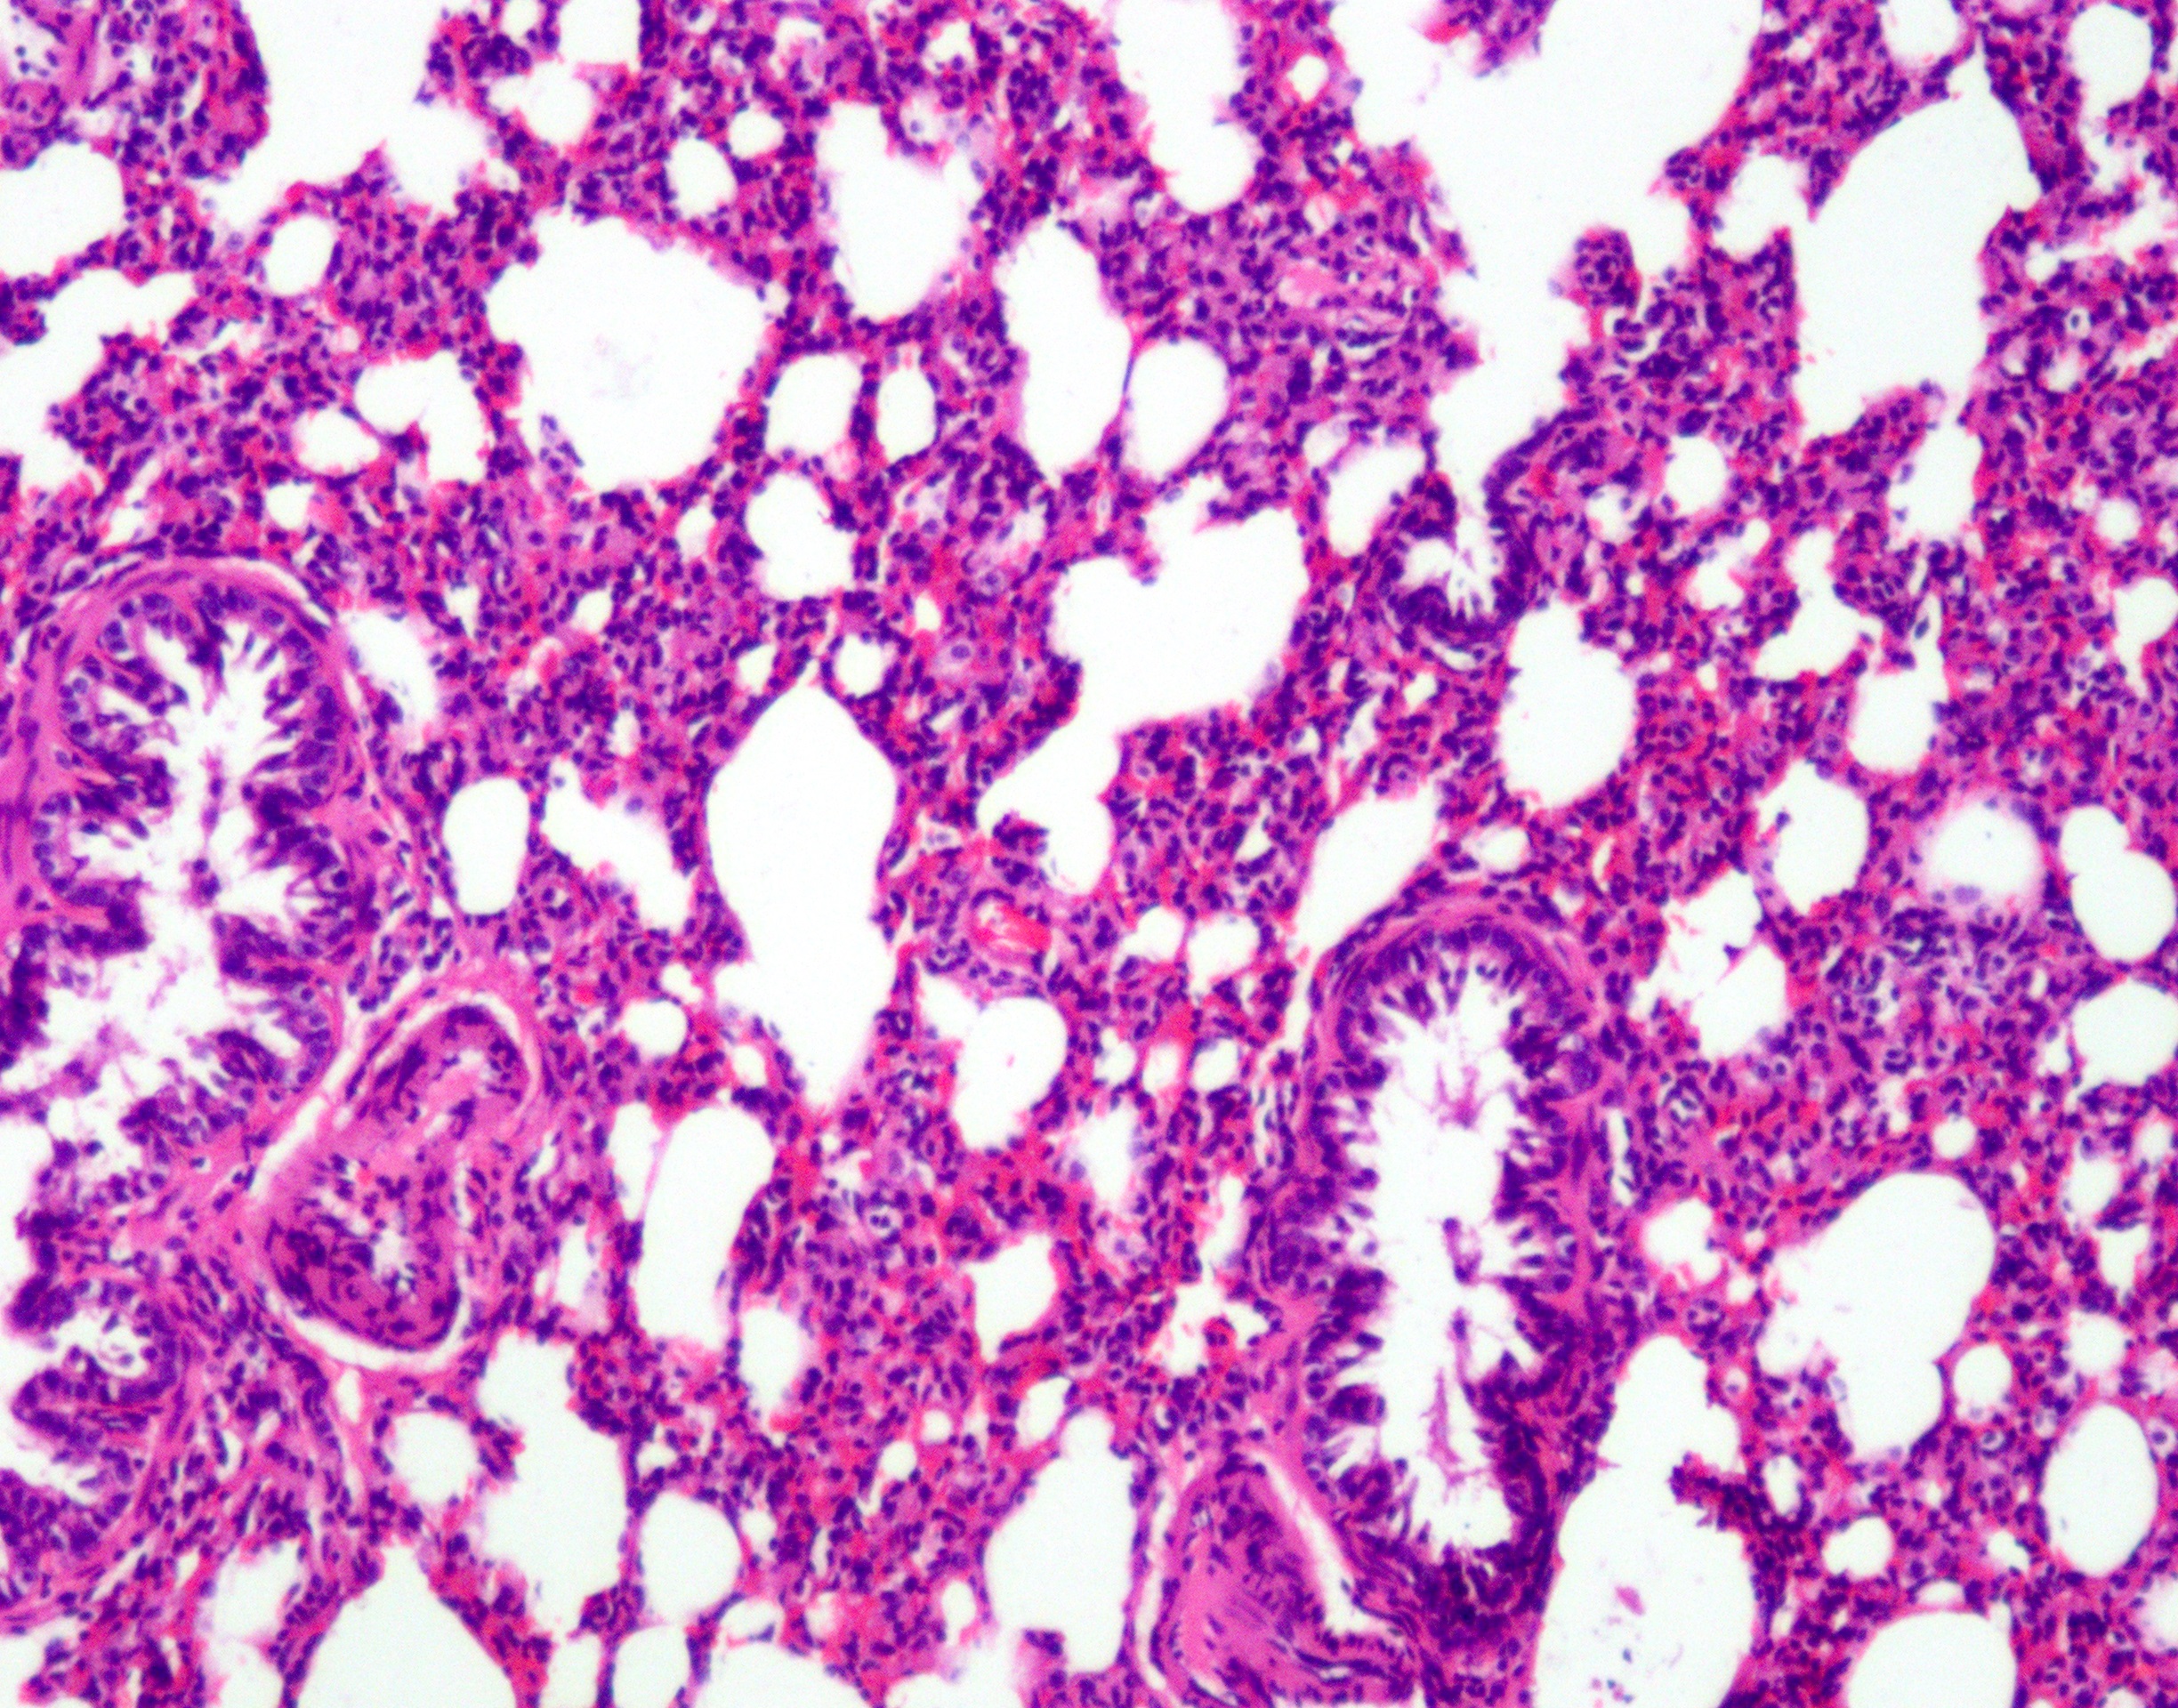

(图示:小鼠肝脏组织HE染色,细胞核呈蓝色,细胞质呈粉红色)

苏木精-伊红染色法(Hematoxylin-Eosin staining),简称HE染色法,是石蜡切片技术中最常用的染色方法。苏木精染液为碱性,主要使细胞核内的染色质与胞质内的核糖体着紫蓝色;伊红为酸性染料,主要使细胞质和细胞外基质中的成分着红色。HE染色法是组织学、胚胎学、病理学教学与科研中最基本、使用最广泛的技术方法。

苏木精-伊红染色法 ( hematoxylin-eosin staining ) ,简称HE染色法 ,石蜡切片技术里常用的染色法之一 。苏木精染液为碱性 ,主要使细胞核内的染色质与胞质内的核糖体着紫蓝色 ;伊红为酸性染料 ,主要使细胞质和细胞外基质中的成分着红色 。HE染色法是组织学、胚胎学、病理学教学与科研中最基本、使用最广泛的技术方法。